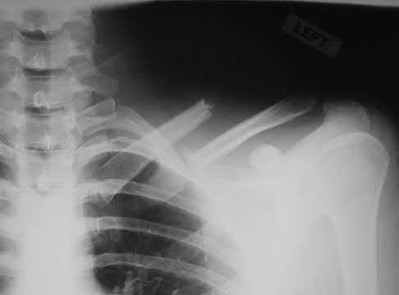

2. # A 35-year-old woman is involved in a head-on collision while driving. Initial radiographs are shown in Figures 8a and 8b. Injury to what vessel increases the risk for osteonecrosis of the injured bone?

5. Artery of the tarsal sinus Corrent answer: 4

The patient has a Hawkins type III talar neck fracture-dislocation with a risk of osteonecrosis ranging from 69% to 100%. Anatomic studies have shown that the artery of the tarsal canal supplies the lateral two thirds of the talar body.

The other vessels listed provide no significant contribution to the talus.